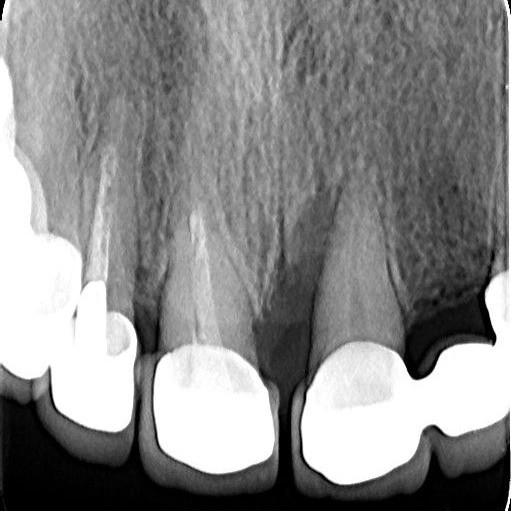

Regenerativni parodontološki zahvat kojim se kirurškim putem regenerirao infrakoštani defekt(parodontološki džep)